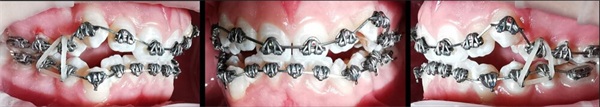

The Fastbraces Technology bracket systems have reduced orthodontic treatment durations to as little as 60–90 days. The case presented here (Figs. 1–5) is a 16-year-old female with a Class I occlusion on both sides, moderate crowding, and an open bite tendency. Interarch vertical elastics were used throughout the treatment.

Fig. 2: March 28

Fig. 3: April 11